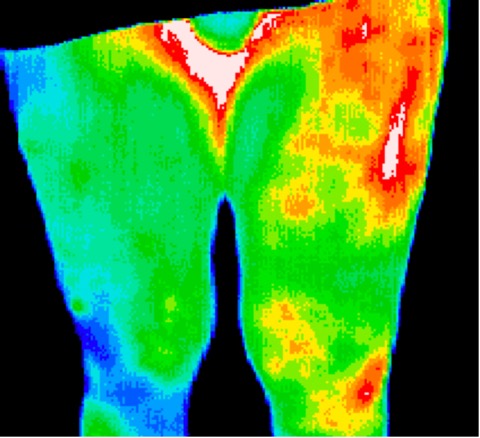

Infected hip replacement